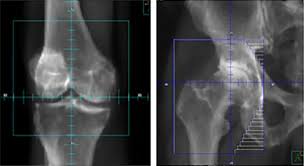

Treatment Planning and Imaging

CT or X-ray imaging guides treatment field design. Medical physicists calculate beam angles and intensities. Computer planning systems optimize dose distribution. Quality assurance checks verify calculation accuracy.

Target volumes include the affected joint plus a small margin. Radiation fields typically measure 6-12 centimeters across. Field sizes adapt to specific joint anatomy. Smaller fields treat finger joints while larger areas cover hip or knee.

Effect low-dose radiotherapy treatment of patients knee osteoarthritis follows established protocols. Both medial and lateral compartments receive treatment when appropriate. Patellofemoral arthritis may require separate field arrangements. Bilateral knee treatment can occur during the same session.

Hip knee and other large joint treatments use similar techniques. Hip positioning may require special devices for comfort. Shoulder treatments accommodate joint mobility limitations. Each anatomical location requires protocol adaptations.

Radiation therapy hand osteoarthritis presents unique challenges. Small finger joints require precise field placement. Wrist arthritis often involves multiple small bones. Lead shielding protects uninvolved fingers during treatment.